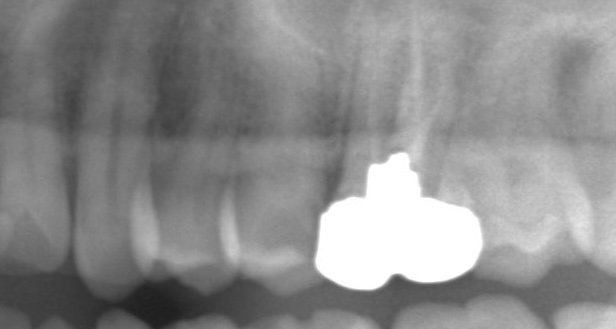

白いところは奥歯に金属がはまっている部分です。

その隣の歯に、”黒い影”があることに気づきますか?

はっきりむし歯があることがわかります。

しかもけっこう大きなむし歯です。

これは強い痛みが出てもおかしくありません。

レントゲン検査をしていれば一目瞭然でわかる大きさのむし歯です。